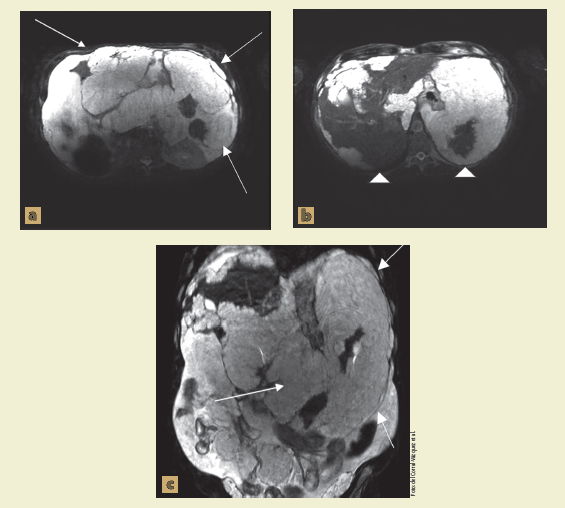

Una vez valorado el resultado, se decidió complementar con resonancia magnética (figura 2) para valorar la extensión del tumor hacia los órganos sólidos, valorando un tumor hiperintenso con importante extensión en el peritoneo, abarcando la mayor parte de la superficie hepática y esplénica.

Figura 2 Se visualizan imágenes de resonancia magnética ponderadas en T2 con supresión grasa, en la imagen a y c (→) se visualiza gran tumoración que se comporta dependiente del mesenterio, con extensión en toda la cavidad abdominal, en la imagen b se visualiza infiltración a la glándula hepática abarcando los segmento IVa, IVb, V, VI y VII, así como en la mayoría de la superficie esplénica.